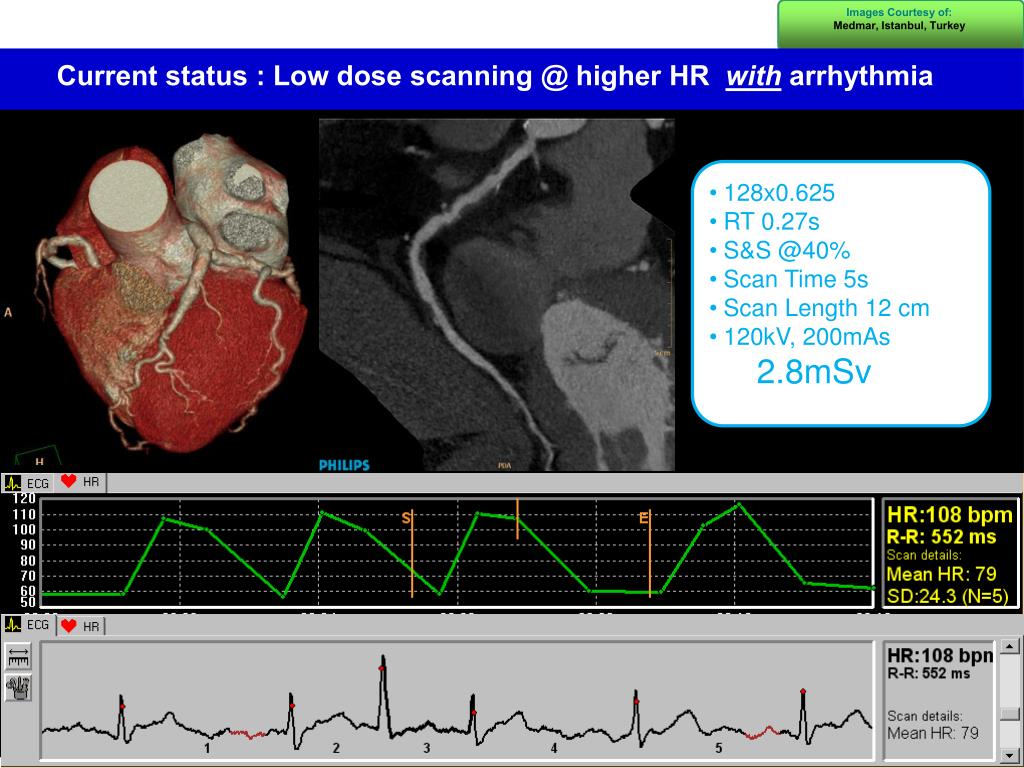

8. Images Courtesy of: Medmar, Istanbul, Turkey • 128x0.625 • RT 0.27s • S&S @40% • Scan Time 5s • Scan Length 12 cm • 120kV, 200mAs • 2.8mSv Current status : Low dose scanning @ higher HR with arrhythmia 3 3